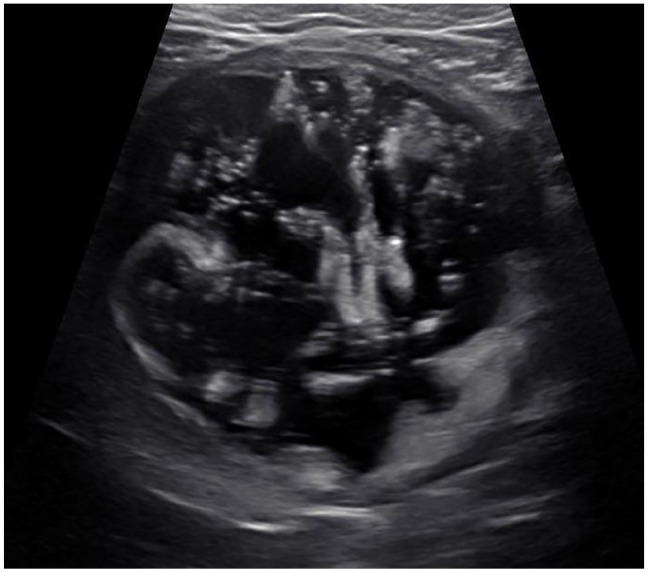

Case summary: A 10-year-old female neutered domestic shorthair cat presented with stranguria. The cat was bradycardic and had a firm urinary bladder on physical examination. On initial laboratory testing, the cat had severe azotemia with a creatinine of 15.8 mg/dl (reference interval [RI] 1.1-2.2), blood urea nitrogen of 217 mg/dl (RI 18-33) and potassium of 8.9 mmol/l (RI 3.5-5.0). Abdominal radiography revealed three cystoliths, with one cystolith suspected of being lodged within the trigone. Ultrasound of the abdomen showed marked suspended echogenic debris within the urinary bladder. Corynebacterium urealyticum was isolated from aerobic bacterial urine culture. A cystotomy was performed, and crystallographic analysis of the removed cystoliths showed they were composed of 94% struvite and 6% calcium phosphate. The cat recovered well and was discharged 2 days postoperatively. Three weeks postoperatively, the cat showed resolution of all clinical signs and azotemia.